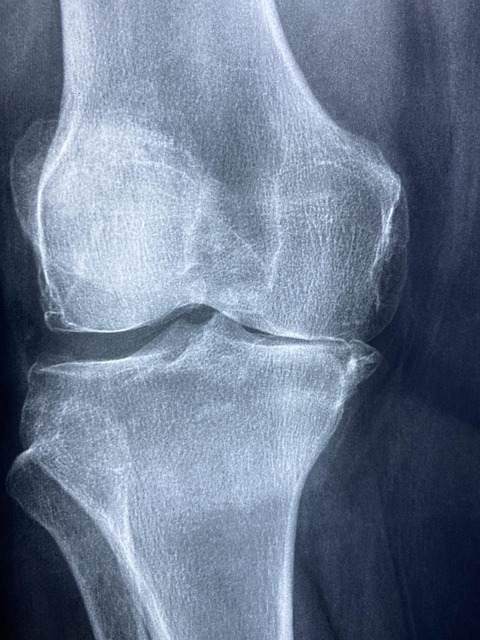

10. 뻣뻣함 및 뚝뚝 소리

관절이 뻣뻣해지고 움직일 때 뚝뚝 소리가 난다면, 이는 관절 마찰이나 연골 손상의 신호일 수 있습니다. 이러한 증상은 초기에는 무시되기 쉽지만, 점차 심각한 문제로 이어질 수 있습니다.

- 통증이 지속되거나 악화되면 즉시 의료 전문가의 조언을 받아 조기 진단을 진행하세요. 조기 치료는 고관절 건강을 회복하는 데 매우 중요합니다.